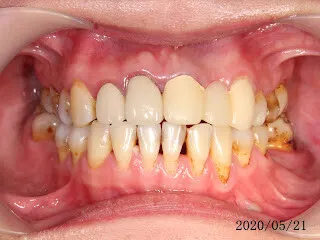

假牙材質2臨床案例...不同的假牙材質+牙齦萎縮